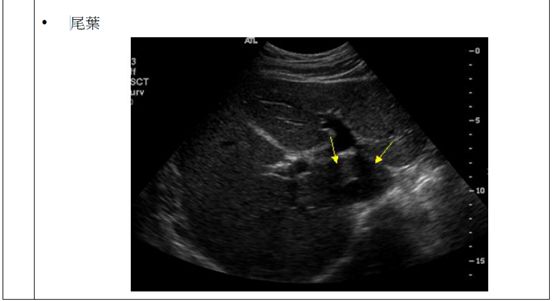

(B)尾葉